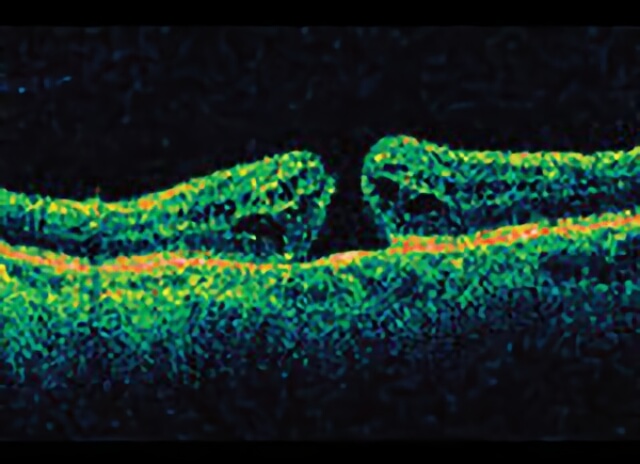

Open macular hole on side view from a special OCT imaging machine.

A macular hole forms in the center of the retina in the back of the eye.